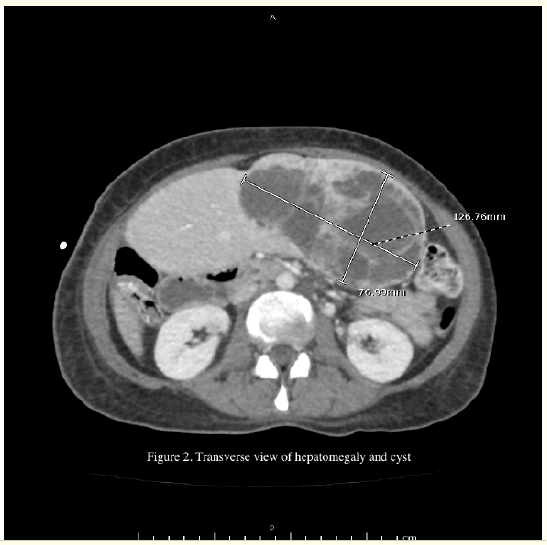

From Gamma Gandy Bodies to Geographic Enhancement: An Imaging Approach to Diagnosing Congestive Splenomegaly

Yassine Zerhari, Asaad El Bakkari, Mohammed Ennmer, Hatim Essaber, Soukaina Allioui, Hounayda Jerguigue, Youssef Omor and Rachida Latib. 6(5): 58-60.